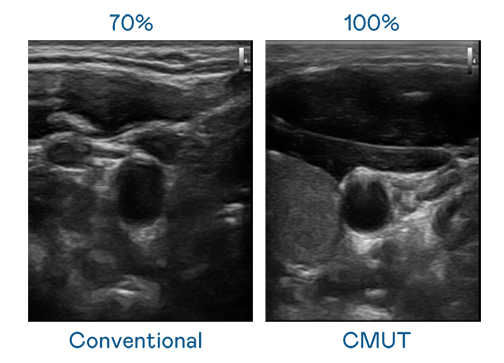

CMUT 技术是一种用电容式微机电元件来产生超音波讯号的技术。与传统 PZT 压电式技术相比,CMUT 频宽增加 30%,更宽频的超音波讯号让影像解析度大幅提升,是实现高影像品质医疗超音波扫描、促进精准医疗发展的关键技术。

大频宽带来超清晰影像

超音波影像的解析度高低,首先取决于探头能发出的讯号频宽。918博天娱乐 CMUT 可提供高清晰的超音波讯号,提供高频宽、高灵敏度、影像纹理细节更高的超音波影像,协助医护人员缩短影像判读时间及利用精准的医疗影像进行诊断。